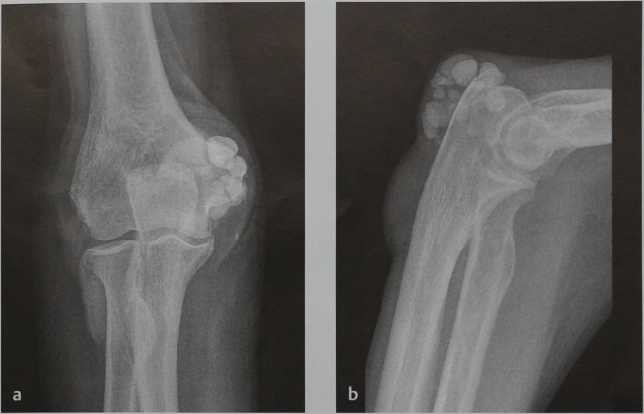

Травмы локтевого сустава

Подразумеваются ушибы локтевого сустава, вывих предплечья, переломы костей, разрыв сухожилия двуглавой мышцы. Стоит знать, что в случае боли, отека, деформации сустава, ограничения движений в локте после травмы обязательно нужно обратиться к врачу для постановки точного диагноза, что возможно сделать только путем проведения рентгенографии.